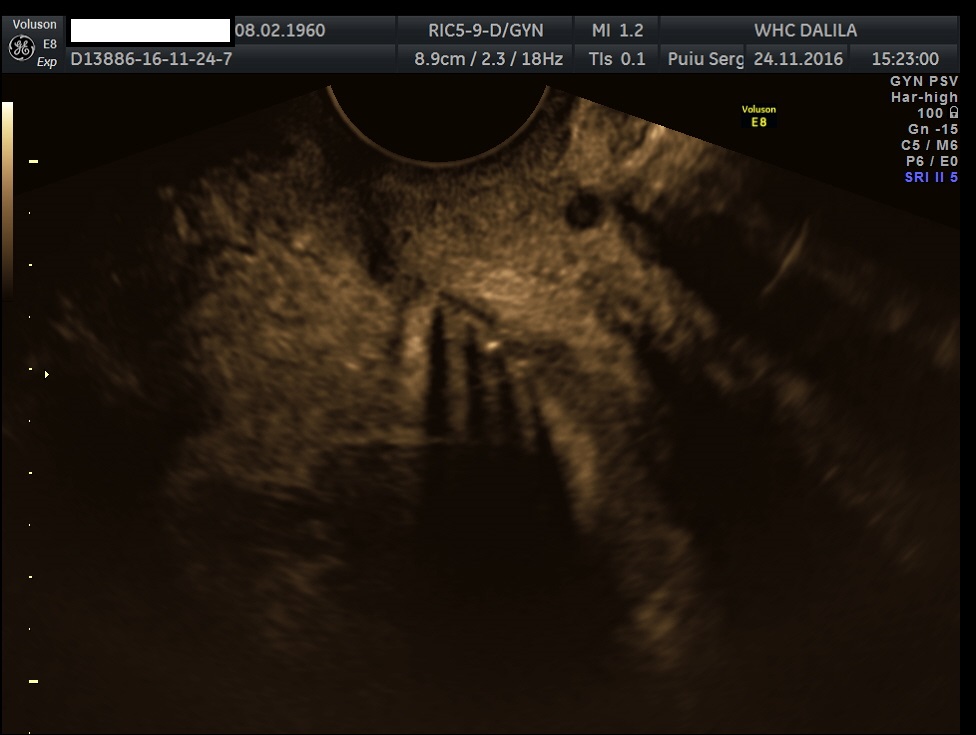

Transvaginal and transabdominal ultrasound scans were performed, which has shown the enlarged uterus with indistinct borders on the left side and a complex mass in left lower abdominal quadrant. A large irregular thick-walled, ill-defined multiloculated cystic/solid lesion with complex fluid collections and peripheral flow on color Doppler were seen. The anatomic distinction between the ovary and the fallopian tube could no longer be identified (Fig. 1). A tubo-ovarian abscess (TOA) was presumed. Endovaginal sonogram showed a dilated uterine cavity and cervical canal, filled with heterogeneous, complex fluid and echogenic masses (Fig. 2a-c). An intrauterine contraceptive was detected. A cavity within myometrium with low-level internal echoes fluid also was revealed (Fig. 2c). This complex adnexal mass was adherent to uterus and a communication between TOA and the cavity within myometrium with fluid-debris level fluid was detected (Fig. 3a-b). This finding presumed a perforation of the TOA into uterus, due to myometrium necrosis, and spontaneous drainages into uterine cavity through myometrium. Increased echogenicity of the pelvic fat and a small amount of free fluid in cul-de sac also were seen. Fluid movements through fistula canal between TOA and uterine cavity were clearly seen when a gently pressure by ultrasound probe was applied (Video 1).

Figures 2a-c. Endovaginal sonograms. Dilated uterine cavity and cervical canal, filled with heterogeneous, complex fluid and masses. An intrauterine contraceptive device also can be easily seen. Note the cavity within myometrium with low level internal echoes fluid and a fluid-fluid level on figure 2c.